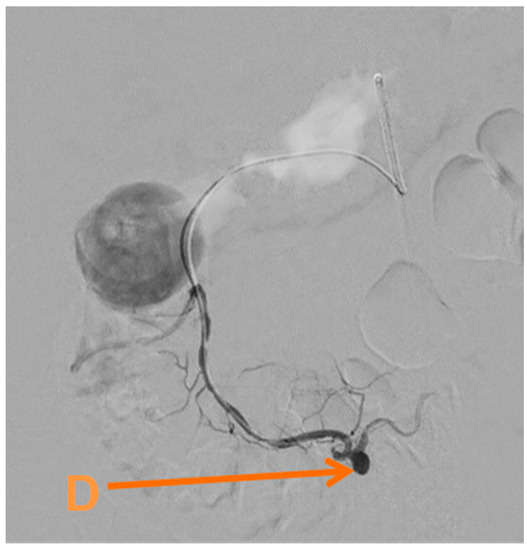

Given her condition and the pathology found, she underwent an embolisation of the inferior pancreaticoduodenal artery via the common femoral artery (Figure 3) on day twenty-six. This was performed using a SIM1 catheter to catheterise the coeliac axis and gastroduodenal artery, revealing reverse flow in the gastroduodenal artery.

Figure 3.

Selective angiogram showing (D) a pseudoaneurysm of the inferior pancreaticoduodenal artery.

Perioperative amylase was elevated at 188 IU/L but improved over time. She did very well and was discharged on the thirty-third day of admission. Though she still had nausea, this was controlled with ondansetron and she was able to eat oral nutrition. She did very well at her follow up and her symptoms had resolved, not requiring re-admission, and awaiting a laparoscopic cholecystectomy.